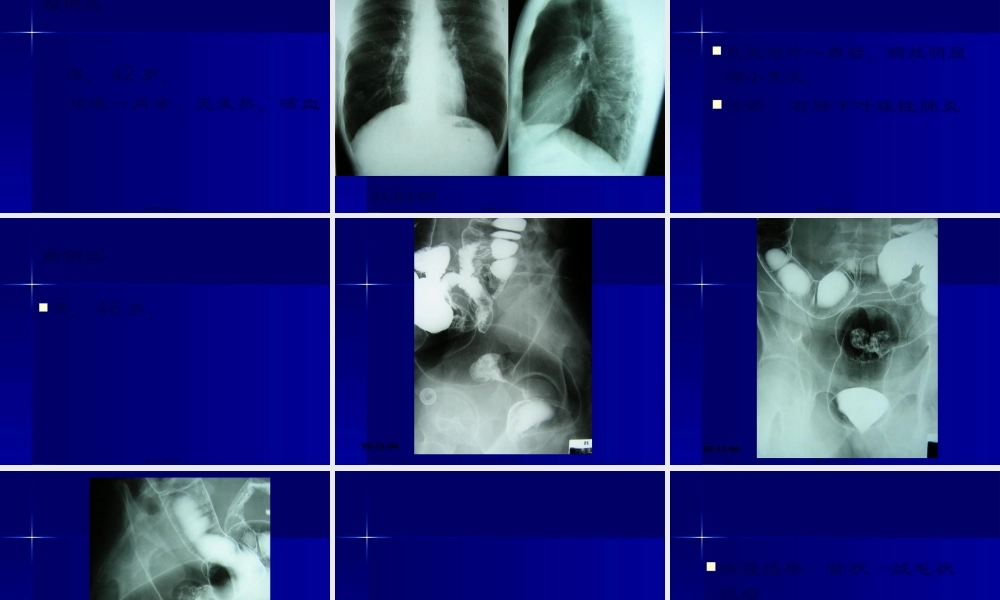

病例一男,52岁,体检发现前纵隔肿物20余天,胸闷、无力,低烧十余天,抗炎治疗后好转。第一页,共三十一页。04-03-11第二页,共三十一页。第三页,共三十一页。第四页,共三十一页。第五页,共三十一页。病理结果:右肺上叶尖段及纵隔慢性肉芽肿性炎症,考虑结核。第六页,共三十一页。病例二男,54岁,咳嗽胸闷一年半,咳血20余天。第七页,共三十一页。04-02-27第八页,共三十一页。第九页,共三十一页。04-02-26第十页,共三十一页。第十一页,共三十一页。第十二页,共三十一页。病理结果:右肺下叶内基底段炎性假瘤第十三页,共三十一页。病例三男,42岁,咳嗽一月余,无发热,咳血第十四页,共三十一页。04-03-05第十五页,共三十一页。抗炎治疗一周后,病灶明显缩小变淡。诊断:右肺下叶球性肺炎第十六页,共三十一页。病例三男,46岁,第十七页,共三十一页。02-11-04第十八页,共三十一页。02-11-04第十九页,共三十一页。第二十页,共三十一页。第二十一页,共三十一页。病理结果:管状—绒毛状腺瘤第二十二页,共三十一页。病例四男,34岁,发现腹部肿物一月。第二十三页,共三十一页。04-02-18第二十四页,共三十一页。第二十五页,共三十一页。第二十六页,共三十一页。第二十七页,共三十一页。04-02-26第二十八页,共三十一页。第二十九页,共三十一页。病理结果:肝左叶肝癌第三十页,共三十一页。内容总结病例一。男,54岁,咳嗽胸闷一年半,咳血20余天。04-02-26。男,42岁,。咳嗽一月余,无发热,咳血。男,46岁,。男,34岁,发现腹部肿物一月。病理结果:肝左叶肝癌第三十一页,共三十一页。